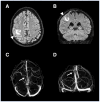

Myelin oligodendrocyte glycoprotein antibody-associated disease (MOGAD) is a central nervous system demyelinating syndrome (DS) typically presenting with optic neuritis or myelitis. The association between cerebral venous thrombosis (CVT) and demyelinating diseases, including multiple sclerosis (MS), is rare. In the present study, a 37-year-old man presented with sensory disturbances in the lower limbs and urinary incontinence, consistent with myelitis. The diagnosis of MOGAD was confirmed by spinal magnetic resonance imaging findings and serum anti-MOG antibody positivity using a cell-based assay. The patient responded successfully to intravenous corticosteroid therapy. However, shortly after recovery, the patient developed a persistent headache and suffered an epileptic seizure, which was later attributed to CVT. The patient was treated with low molecular weight heparin and lacosamide and subsequently returned to baseline health status without seizure recurrence in the following year. Comprehensive review of the literature on CVT associated with DS, encompassing 15 case reports, two case series and two studies, underscores the rarity of this condition. Most reported cases of CVT have been linked to MS, while only three cases of CVT associated with MOGAD have been documented to date. Additional risk factors, such as lumbar puncture and high-dose corticosteroid treatment, have been implicated in some instances. Given their shared inflammatory basis, a thrombotic-inflammatory pathogenic mechanism acting between DS and CVT in predisposed individuals is plausible. However, the exact pathogenic association between these conditions remains largely unclear, and a coincidental association cannot be ruled out. The role of anti-MOG antibodies in this rare condition also warrants further investigation.